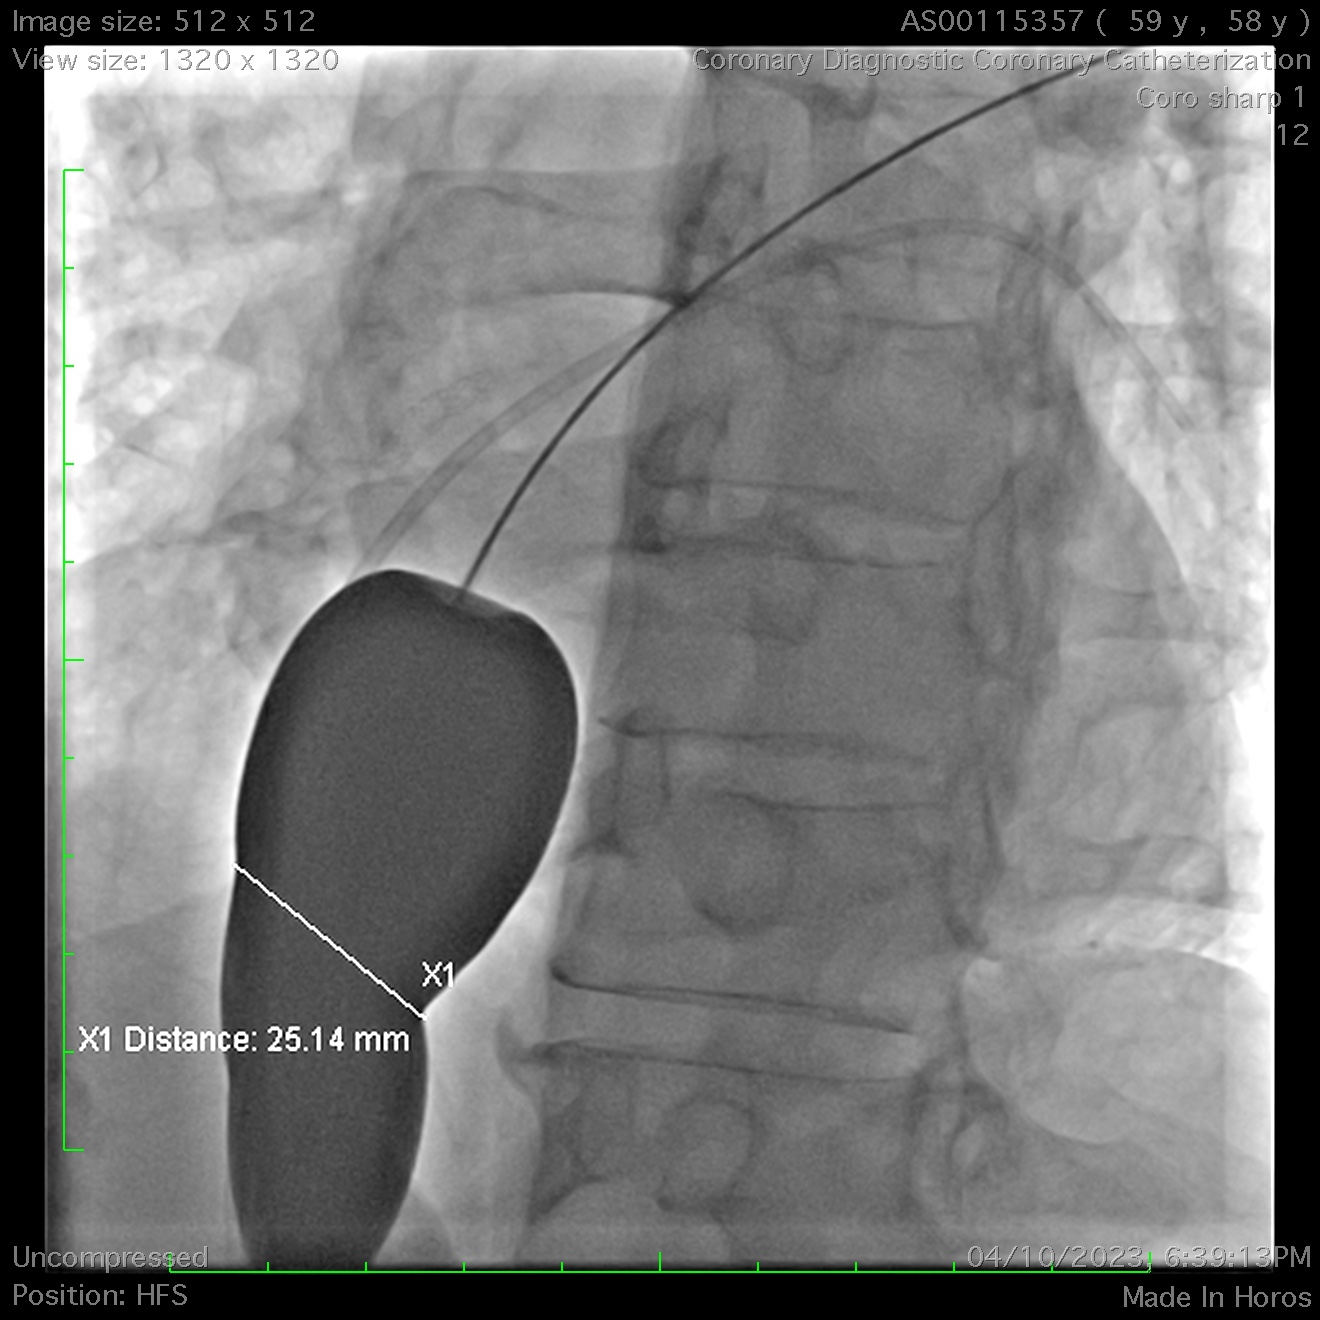

A right heart catheterisation was done, With Fick’s method revealing the pulmonary vascular resistance 2.83 wood unit indicating the need for ASD’s closure. A significant discrepancy arose in determining the true diameter of the ASD. In contrary to previous echocardiography, a repeated peri-procedural TTE measured it at 32mm with balloon inflation to occlude the defect. A decision was made to use a size 36mm occluder.

A 36mm ASD occluder was successfully deployed after confirming optimal position & stability. Unfortunately, post-release, the device embolized into the right ventricle. Agilis steerable catheters were inserted to bilateral femoral veins. Initial attempts to snare the occluder's hub with a single-loop snare proved challenging due to its high mobility within the right ventricle, even when stabilized with a steerable mapping catheter. A modified snare with a larger loop, made from a guiding catheter, coronary wire, and balloon, was employed but failed to capture the hub after multiple attempts.